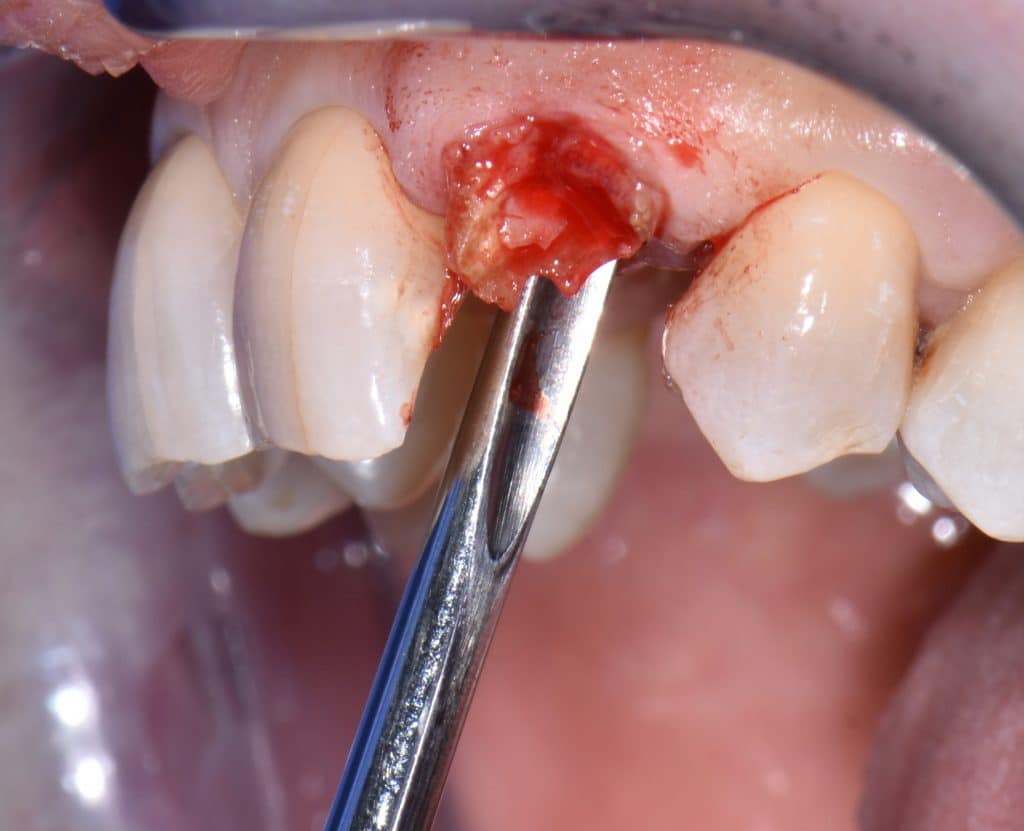

La pz N.G. di anni 52 (ASA 1) viene visitata nel mese di settembre 2017 per la mobilità ed inestetismo dell’elemento protesico 22, (foto iniziali sequenza 1) si evidenzia una frattura parziale della radice, si decide per l’estrazione ( foto sequenza 2) e sostituzione dell’elemento con un restauro implanto-protesico. Purtroppo la scarsa quota ossea apicale all’alveolo post-estrattivo (foto 2 rx) e l’alta valenza estetica dell’elemento ci rende cauti e si programma una socket preservation post estrattiva con l’ausilio delle membrane di prf (foto prf e socket sequenza 3 e 4). Durente i 5 mesi di guarigione la pz porta una protesi parziale mobile (foto 5,2) , a guarigione del sito post estrattivo si evidenzia una buona conservazione dei volumi osseo-gengivali,(foto guarigione sequenza 6) se pur presente una recessione distale all’elemnto 21.Nel mese di febbraio 2018 si procede all’inserimento di un impianto max-stability 3,75x12mm disegnando un lembo anticipato palatino per consentire un aumento dei tessuti vestibolari suturando con tecnica rool flap e trasformando l’elemento parziale mobile in una corona singola a carico immediato sul moncone temporameo applicando i concetti protesici bopt , (foto impianto moncone protesi provvisoria sequenza foto 7-8-9). Durante il periodo di maturazione dei tessuti molli vengono apportate opportune modifiche ai profili del provvisorio al fine di dare maggior spazio al tessuto gengivale, ( fotosequenza 10).Dopo circa 2 mesi dal protesizzazione provvisoria si è proceduto alla realizzazione del manufatto protesico con tecnica chair side sirona con l’ausilio del t-base (foto sequenza 11-12-13), realizzando in una sola seduta una corona in disilicato, ottenendo un risultato più che soddisfacente (Foto 14). Nel controllo a 3 mesi dal carico definitivo si apprezza la perfetta conservazione dei livelli ossei e gengivali. (foto sequenza 15).concludo con un follow up a 18 . Tengo a sottolineare che un caso come questo è stato conducibile con buoni risultati solo grazie alla piena fiducia della pz e alla sua massima motivazione e collaborazione. Ad oggi la pz sorride soddisfatta del risultato. E questo rappresenta la massima ricompensa di chi dedica tutto se stesso alla professione.